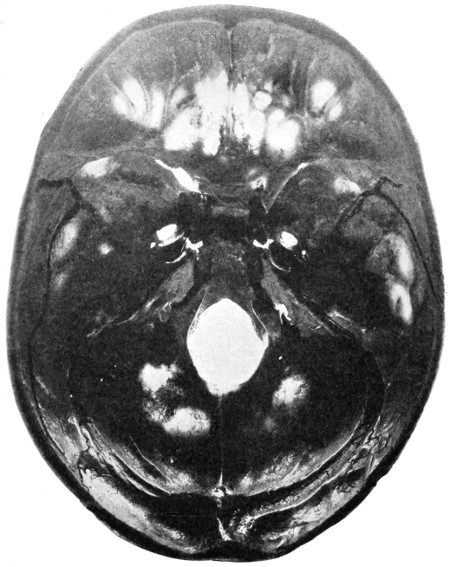

| 50 A and B. The inner aspect of the skull and the same seen on transillumination | 137 |

| 51. To illustrate compression of the brain as produced by an extra-dural hæmorrhage from the middle meningeal artery[x] | 141 |

| 52 A and B. The operative treatment of middle meningeal hæmorrhage | 144, 145 |

| 53. A basic fracture with laceration of both carotid arteries | 148 |

| 54. A basic fracture with laceration of the cavernous sinus | 149 |

| 55. A basic fracture with laceration of both lateral sinuses | 151 |

| 56 A and B. The operative treatment of subdural hæmorrhage | 156, 157 |